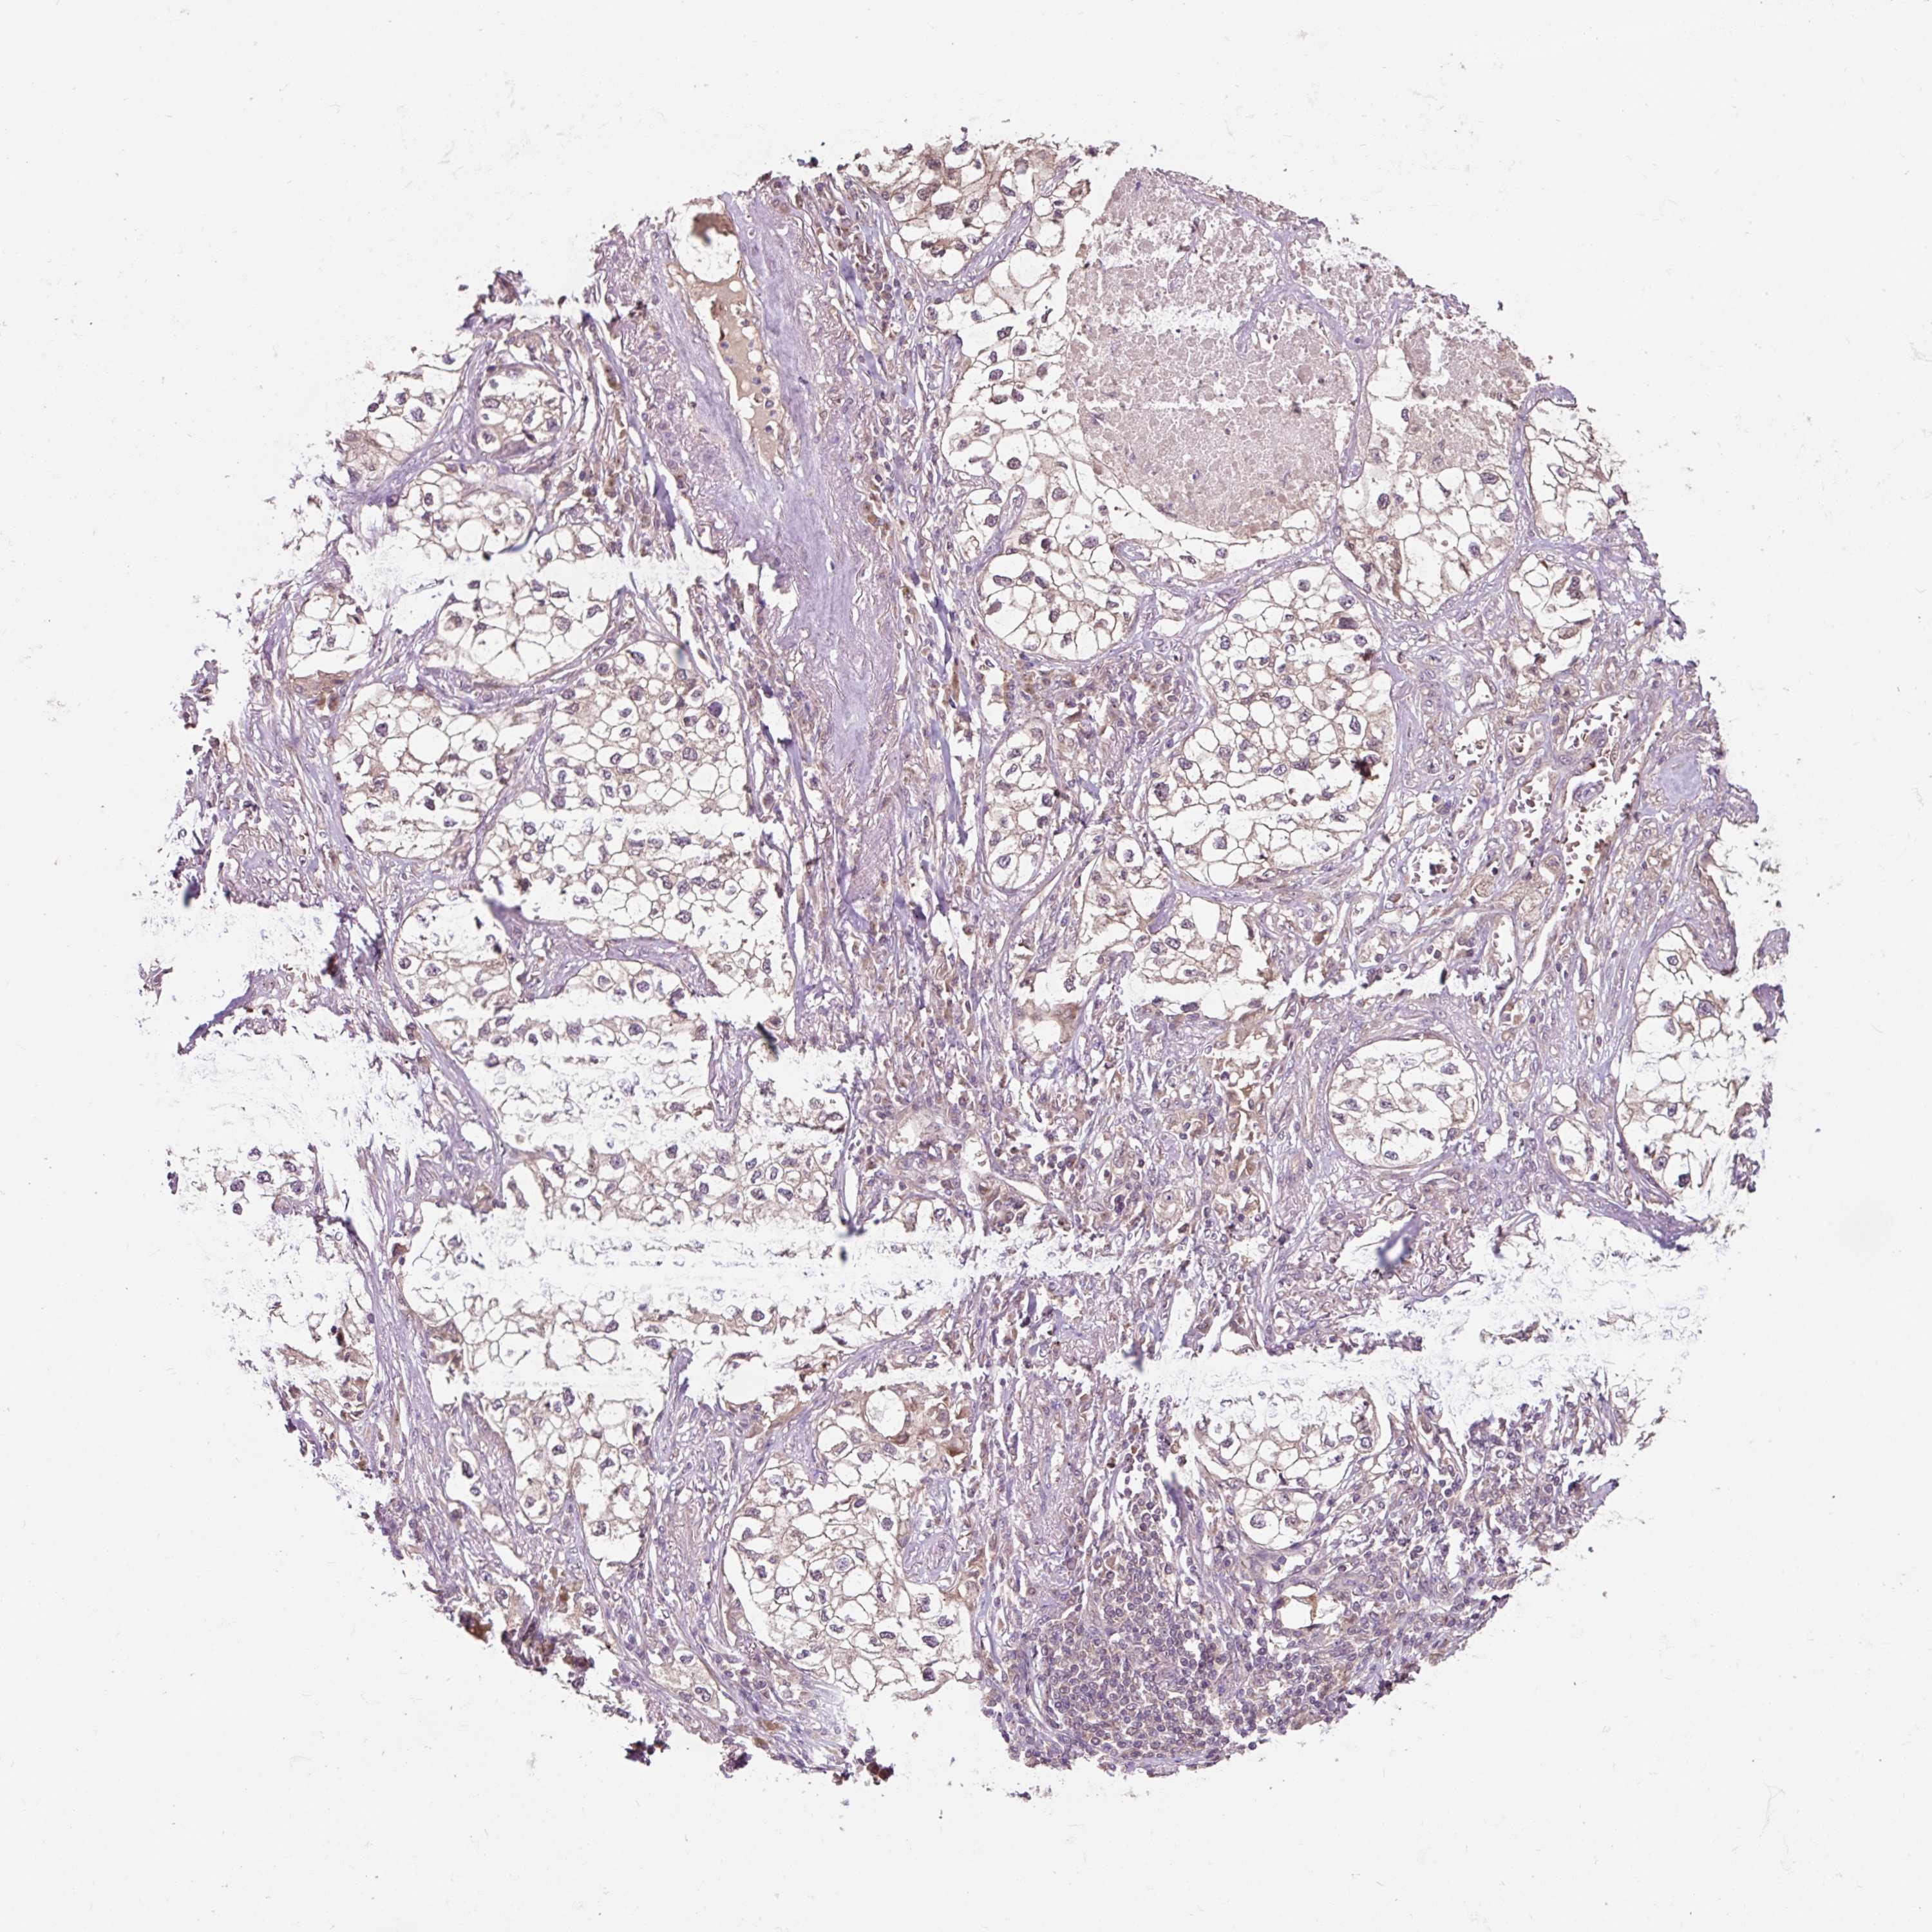

CANCER LUNG CANCER Show tissue menu

LUAD TCGA LUAD VALIDATION LUSC TCGA LUSC VALIDATION PROTEIN LUAD CPTAC PROTEIN LUSC CPTAC PROTEIN EXPRESSION

ANTIBODIES

AND

VALIDATION